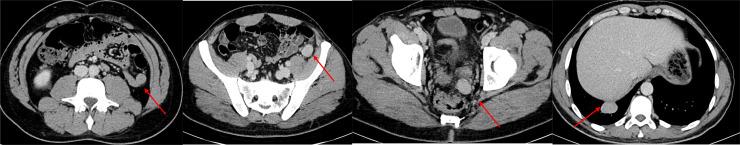

A 37-year-old male patient presented complaining of right flank pain. As an incidental finding on CT, the spleen was not visualized and there were multiple rounded peritoneal tissue nodules, radiologically pattern is mostly suggestive of splenosis. Lung bases showed 2 right lower lung lobe nodules. A dedicated chest CT scan revealed few other pulmonary and pleural nodules. A 99mTc heat damaged denatured red blood cells SPECT CT scan was performed, which revealed right thoracic splenosis, a rare entity to be seen at that location.